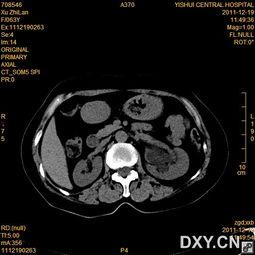

肾积水,顾名思义,就是肾脏内尿液积聚过多,导致肾脏体积增大,甚至可能引发肾功能损害。肾积水手术,就是通过手术方法,解决肾积水问题,恢复肾脏正常功能。

4. 探查肾脏:医生通过手术器械,探查肾脏内部情况,了解肾积水的具体位置和程度。